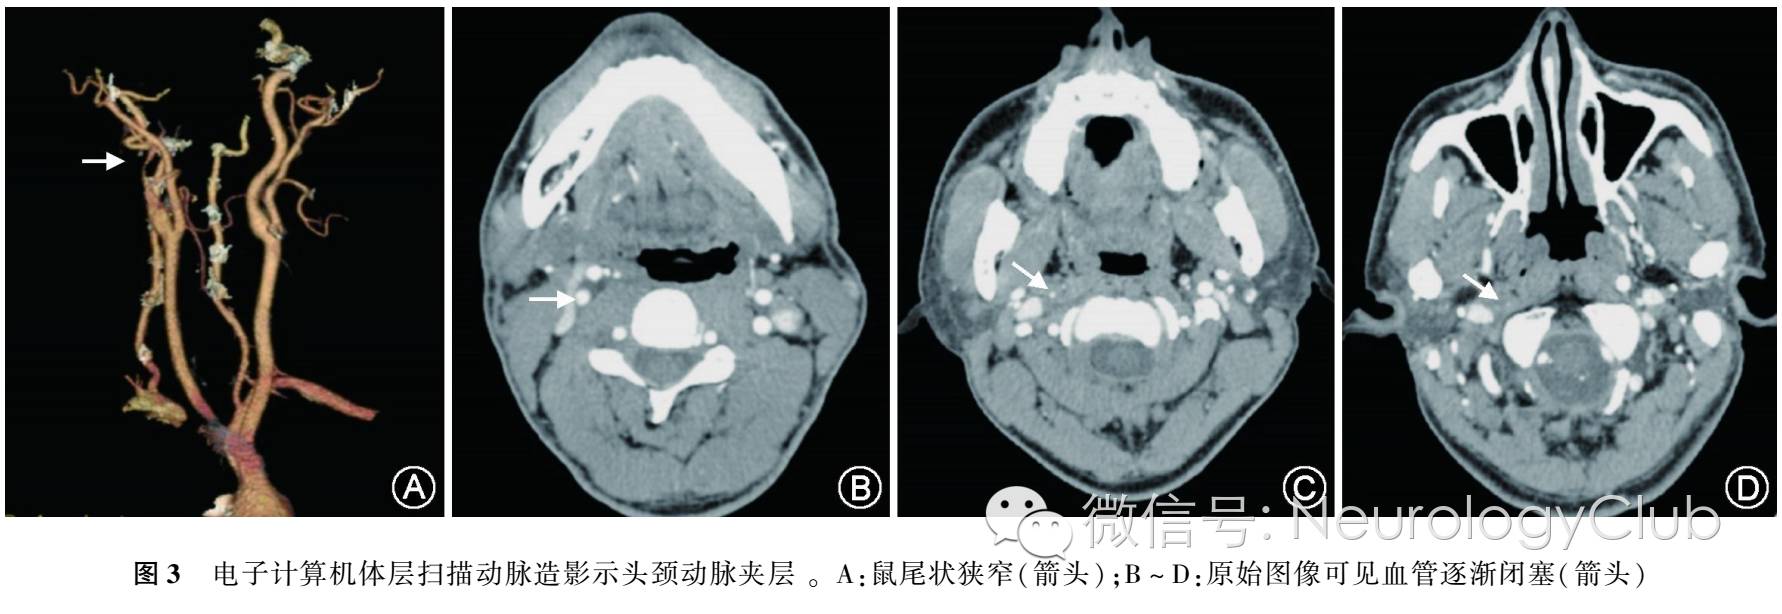

(二)CTA对颅内外动脉夹层的诊断

CTA原始图像可以看到颈内动脉夹层的狭窄管腔,轴位有半月形的壁间出血呈高密度影,可以看到血管的逐渐闭塞(图3)。重建图像可以清楚看到狭窄的位置长度,甚至可以看到夹层掀起的内膜,可见鼠尾状狭窄。CTA诊断椎动脉夹层的敏感度和特异度分别为100%和98%。由于解剖结构和解剖部位的特殊性,颅内椎动脉的动脉瘤样扩张通常发生在V4段,而颅外椎动脉夹层常发生在V3段。当出现特定的影像学征象,如假性动脉瘤、内膜撕裂或双腔外观时,可明确诊断为椎动脉夹层,约<10%的椎动脉夹层会出现上述征象。CTA在诊断颅颈动脉夹层时较MRA有如下优势:可用于夹层超急性期的诊断;动脉周围的静脉丛及脂肪不会干扰CTA成像;更高的空间分辨率可辨别微小动脉夹层。